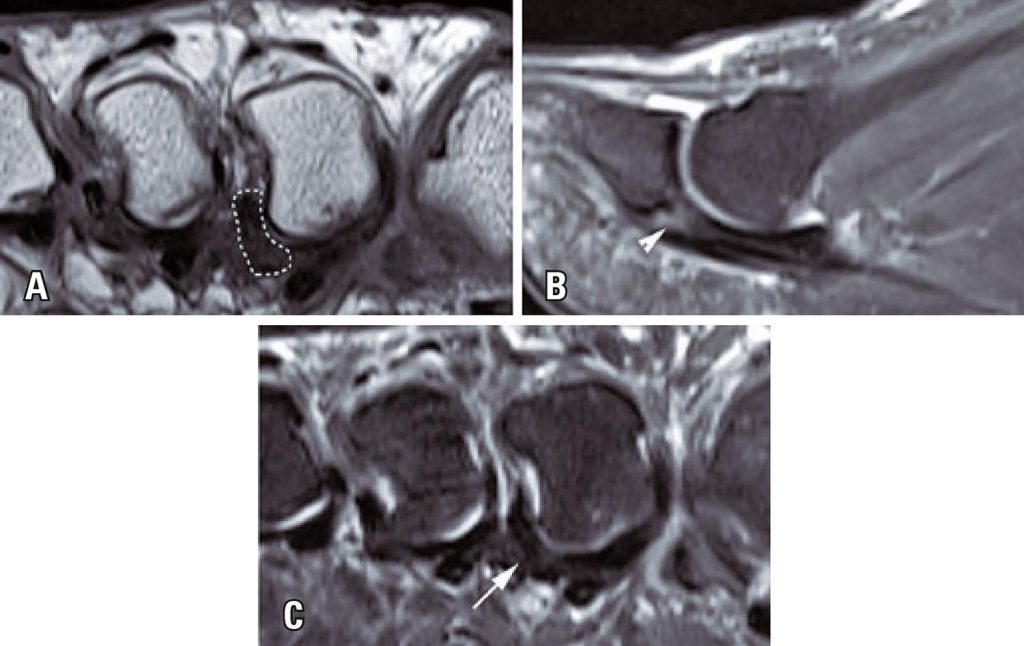

A normal plantar plate was observed in 75 (71.4%) of the 105 feet assessed, in 25 (24%) feet there were degenerative plantar lesions, and in 5 (4.6%) feet there were complete ruptures. Degenerative injury of the plantar plate was best identified in coronal short axis intermediate-weighted images, with high sensitivity (92%). Pericapsular fibrosis below the intermetatarsal ligament was identified in 96% of cases, with high sensitivity (96%) for diagnosis of degenerative plantar plate injury.

Degenerative lesions of the metatarsophalangeal plantar plate were more prevalent than complete ruptures and were best viewed in coronal short axis intermediate-weighted sequences. Pericapsular fibrosis below the intermetatarsal ligament was the indirect finding most strongly associated with degenerative plantar plate injury.